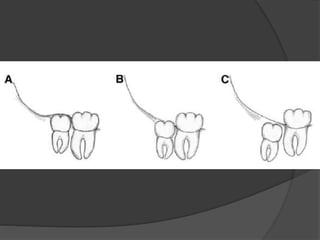

Classifications

 Based on depth: according to relationship with the

occlusal surface of adjoining second molar between

long axis of 2 molar & ascending ramus.

 Position A - highest position of the tooth is on a level or

above the occlusal line.

 Position B - highest position is below the occlusal line

but above the cervical level of second molar.

 Position C - highest position is below the cervical level

of second molar.